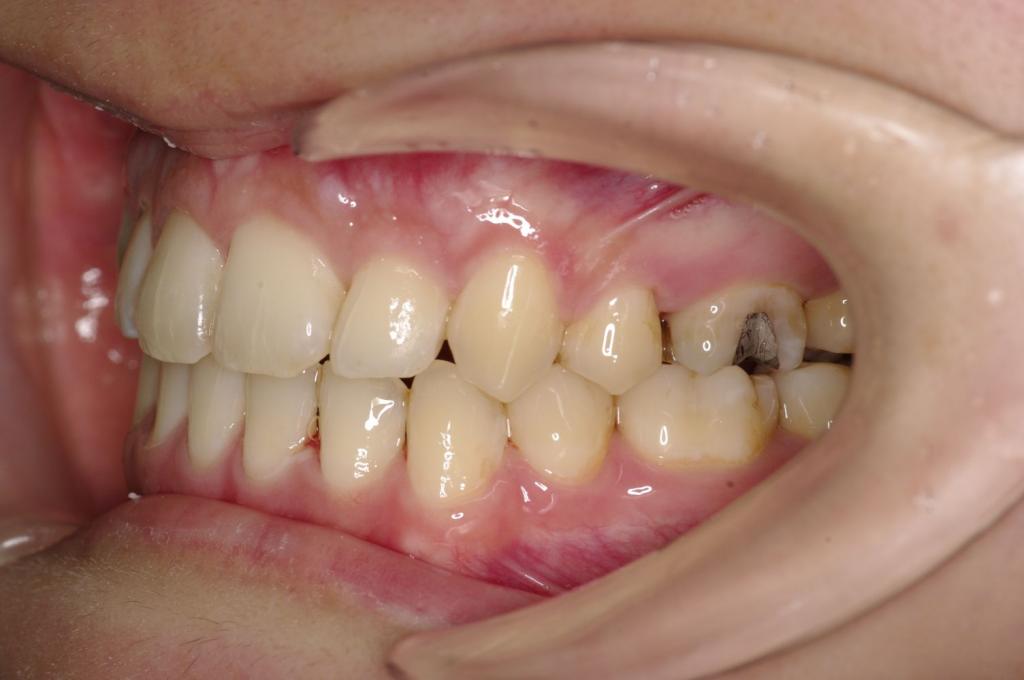

前歯、出っ歯・開咬の矯正治療

(治療期間、治療前後写真、治療方法、費用)WORKS

- 歯根の吸収:歯が動く時に、まれに歯の根の先がとけたり、歯の根が細くなったりすることがあります。